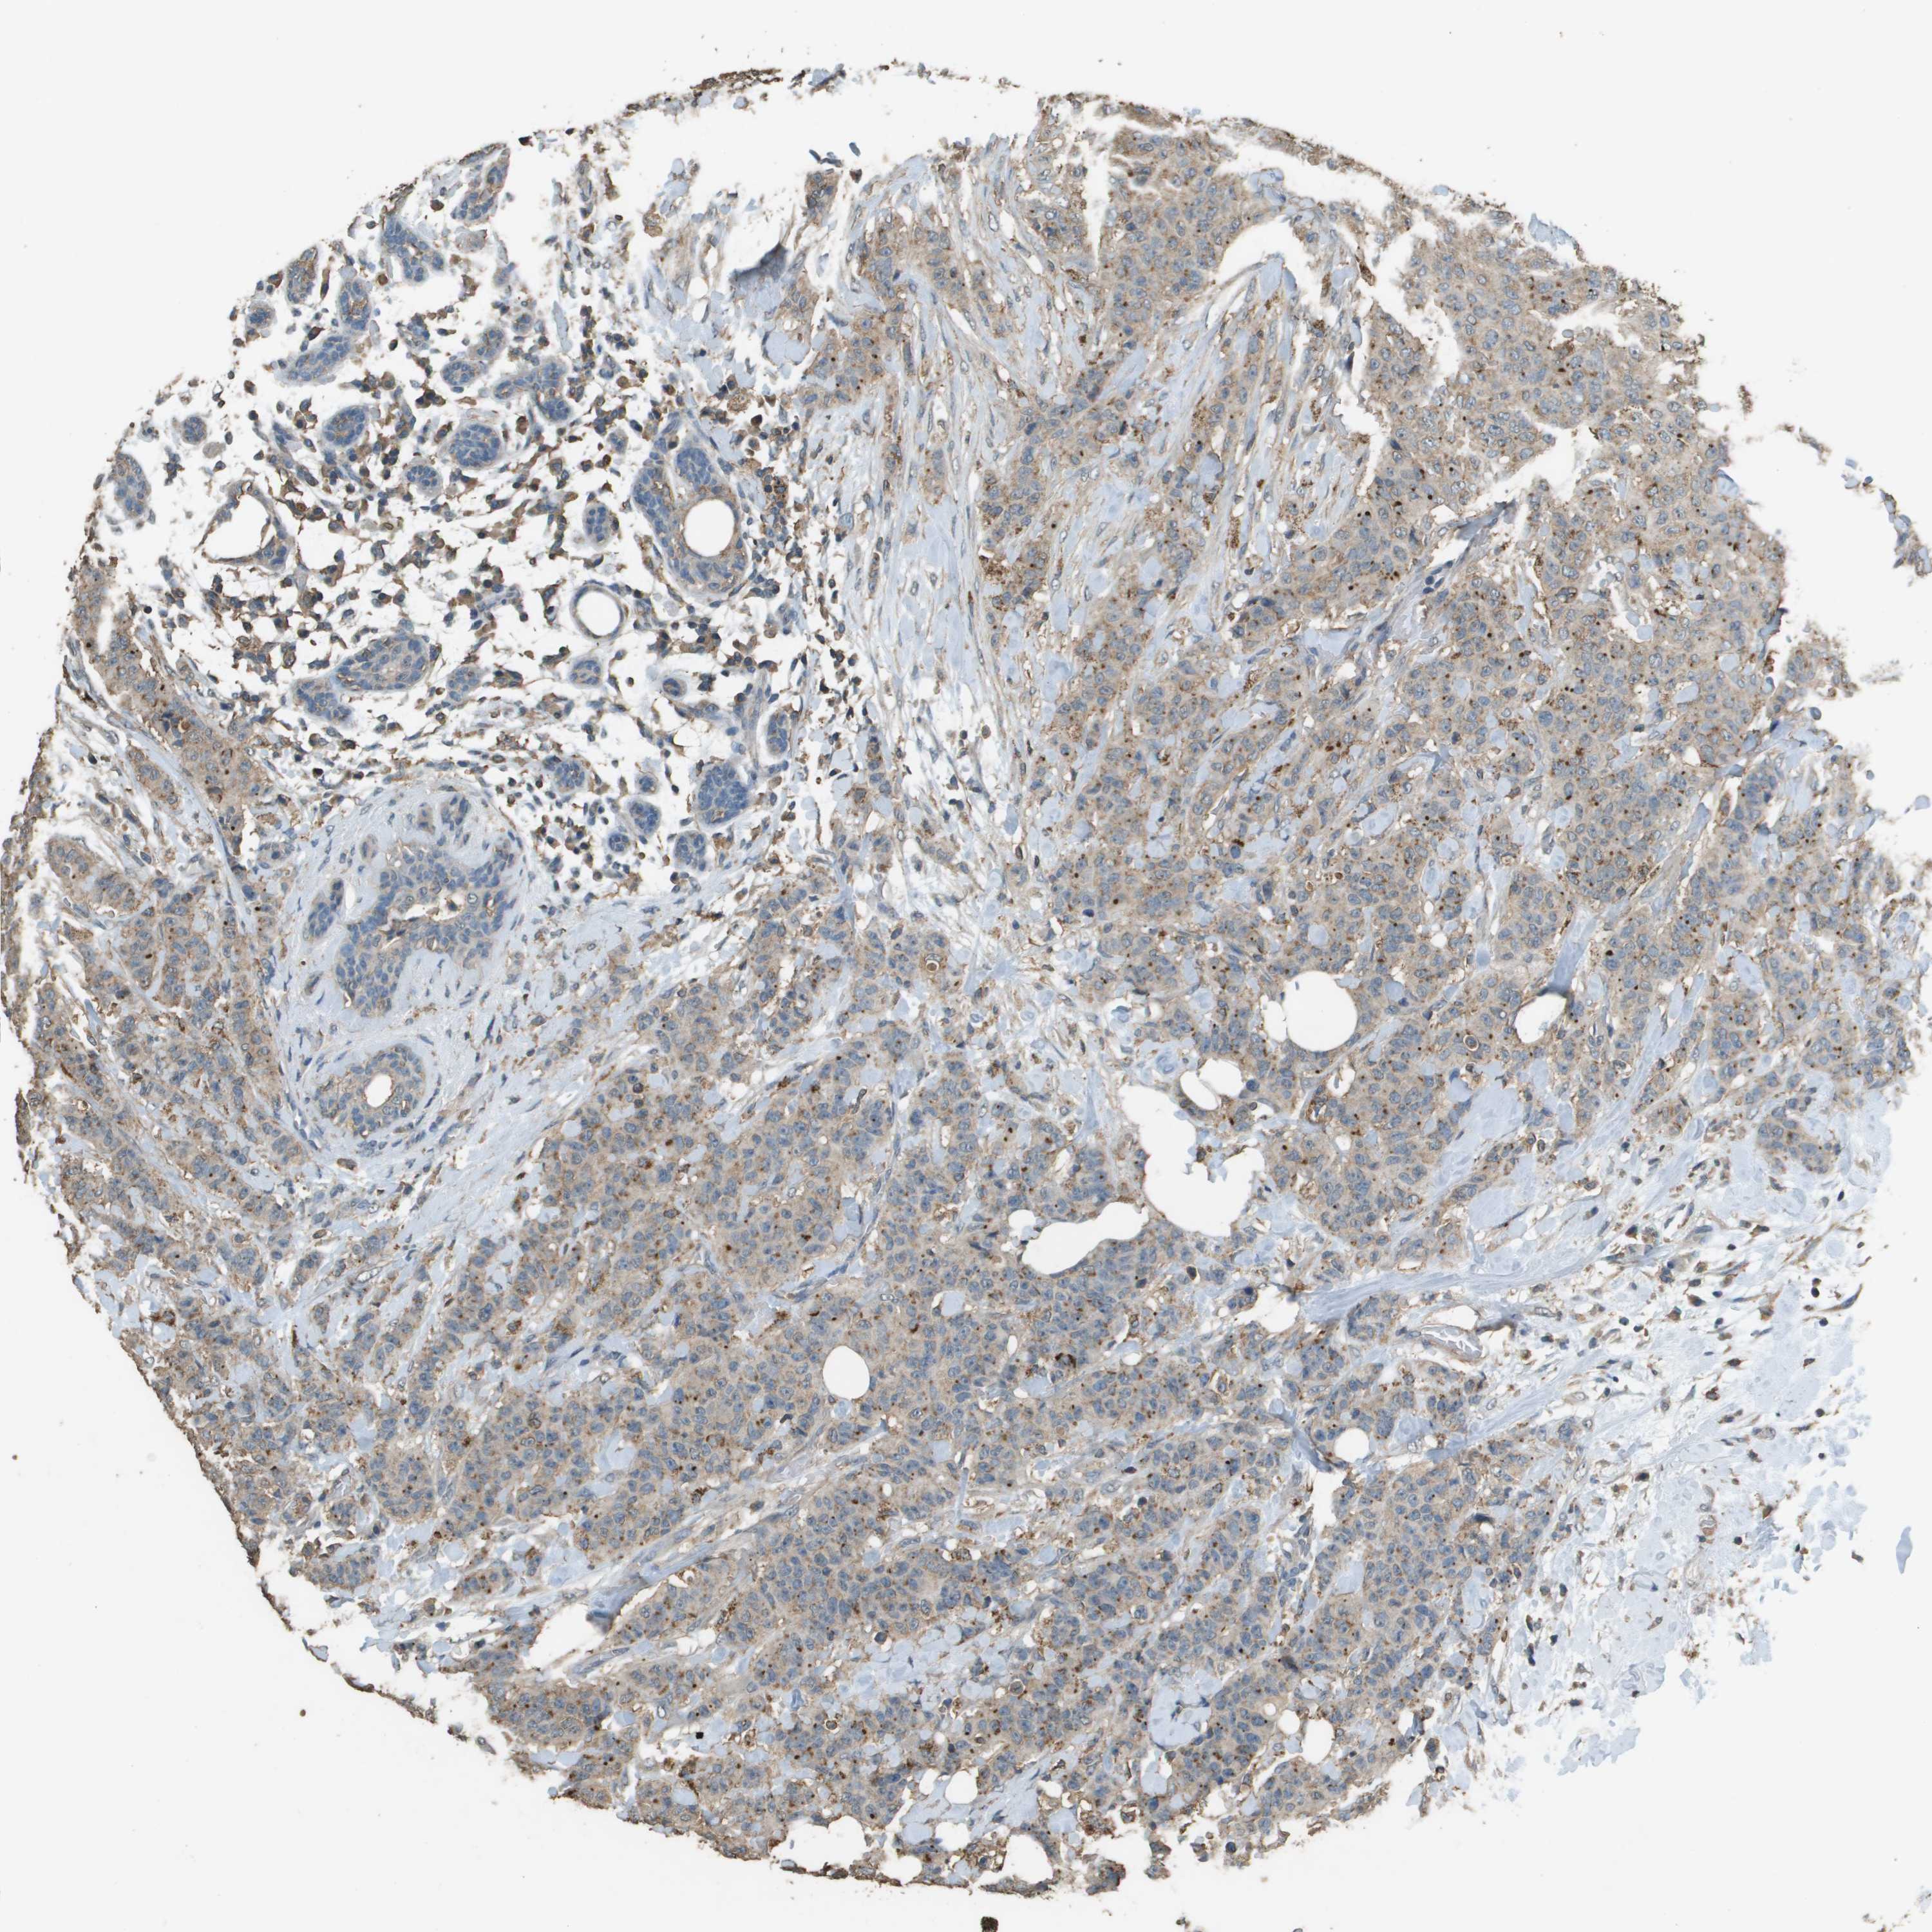

CANCER BREAST CANCER Show tissue menu

BRCA TCGA BRCA VALIDATION PROTEIN EXPRESSION